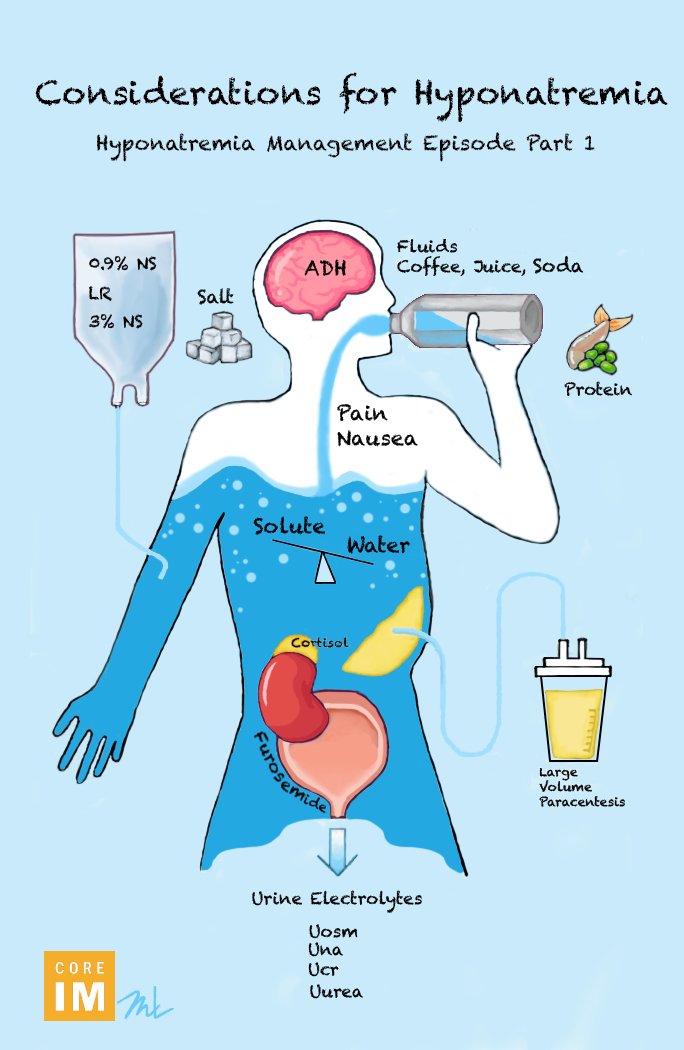

Avraham Z. Cooper, MD 🩺 Cannon ball app in lung via hematogenous spread Choriocarcinoma..raised hcg levels Other signs- • hyperthyroidism( as alpha subuit of hcg~ TSH,Lh,fsh) •Gynecomastia D/D: CRASH C- CHORIOCARCINOMA R- RCC A- ADRENAL S- SYNOVIAL SARCOMA H- his- prostate Her- endometrial